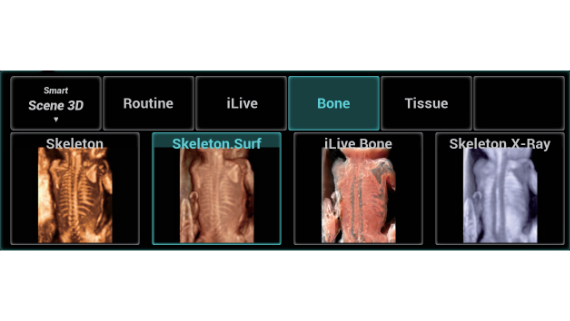

El sistema Nuewa I9, dise?ado exclusivamente para la atenciĂłn mĂ©dica neonatal y de mujeres, brinda una experiencia innovadora integral. Estas innovaciones se desarrollan sobre la base de un conocimiento profundo de situaciones clĂnicas complejas para proporcionar respuestas precisas y oportunas, una gran eficiencia y una experiencia de usuario extraordinaria.

La plataforma ZST+?es una innovaciĂłn extraordinaria que representa toda una evoluciĂłn en el ĂĄmbito de la ecografĂa. Transforma las mĂ©tricas ecogrĂĄficas de la formaciĂłn de haces convencional al procesamiento basado en datos de canal. Supera la limitaciĂłn tradicional de tener que equilibrar entre resoluciĂłn espacial, resoluciĂłn temporal y uniformidad del tejido, con lo que ofrece una calidad de imagen excepcional para soluciones de producciĂłn de imĂĄgenes infinitas con mejoras continuas.